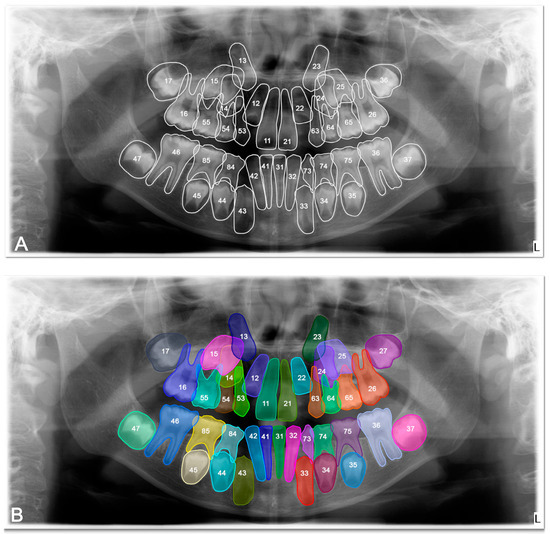

Artificial Intelligence-Based Evaluation of Permanent First Molar Extraction Indications in Children Using Panoramic Radiographs

Background: The aim of this study was to develop an artificial intelligence (AI)-based decision support model for evaluating the extraction indication of permanent first molars in pediatric patients using panoramic radiographs, and to investigate the potential contribution of this model to the clinical decision-making process. Methods: This retrospective observational study analyzed 1000 panoramic radiographs obtained from children aged 8–10 years who attended the Clinics of Batman University Faculty of Dentistry for routine dental examination. Among the radiographs meeting the inclusion criteria, a total of 176 panoramic images were selected based on dental maturation assessment using the Demirjian tooth development staging system. Cases in which the permanent second molar was classified as Demirjian stages E–F were labeled as “extraction indication present”, while the remaining stages were labeled as “extraction indication absent”. A balanced dataset was created, consisting of 88 cases in each group. Image features were extracted using Gabor filters and Histogram of Oriented Gradients (HOG). The selected features were analyzed using a Support Vector Machine (SVM) classifier with a radial basis function (RBF) kernel. Model performance was evaluated using accuracy, sensitivity, specificity, F1-score, and area under the receiver operating characteristic curve (ROC–AUC). Results: The proposed Gabor–HOG–SVM-based AI model achieved an overall classification accuracy of 77.78% with an AUC value of 0.77 in distinguishing between “extraction indication present” and “extraction indication absent” cases. For the extraction-indicated group, the sensitivity was 0.81 and the F1-score was 0.79, whereas for the non-indicated group, the sensitivity and F1-score were 0.74 and 0.77, respectively. No statistically significant differences were observed between the groups in terms of age or sex distribution (p > 0.05). Conclusions: This study demonstrates that artificial intelligence-based analysis of panoramic radiographic images can provide an objective and reproducible decision support approach for evaluating extraction indications of permanent first molars in pediatric patients. The proposed model should be considered as an adjunctive tool to reduce observer-dependent variability rather than a replacement for clinical judgment, and its clinical applicability should be further validated through multicenter and multi-parametric studies. Full article